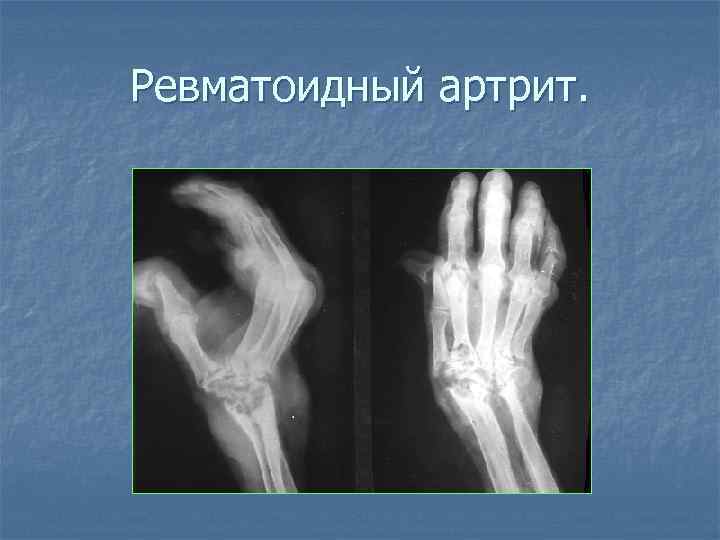

Ревматоидный артрит.